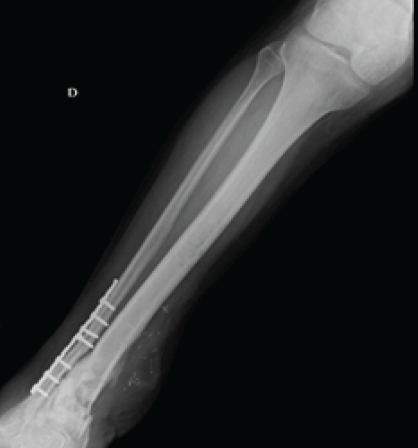

Radiological assessment (radiograph, computed tomography-scan, and magnetic resonance imaging) showed osteitis of the distal tibia over an area of 9 cm (Figs. 2 and 3).

Figure 2: X-ray on admission showing osteitis of the distal tibia.